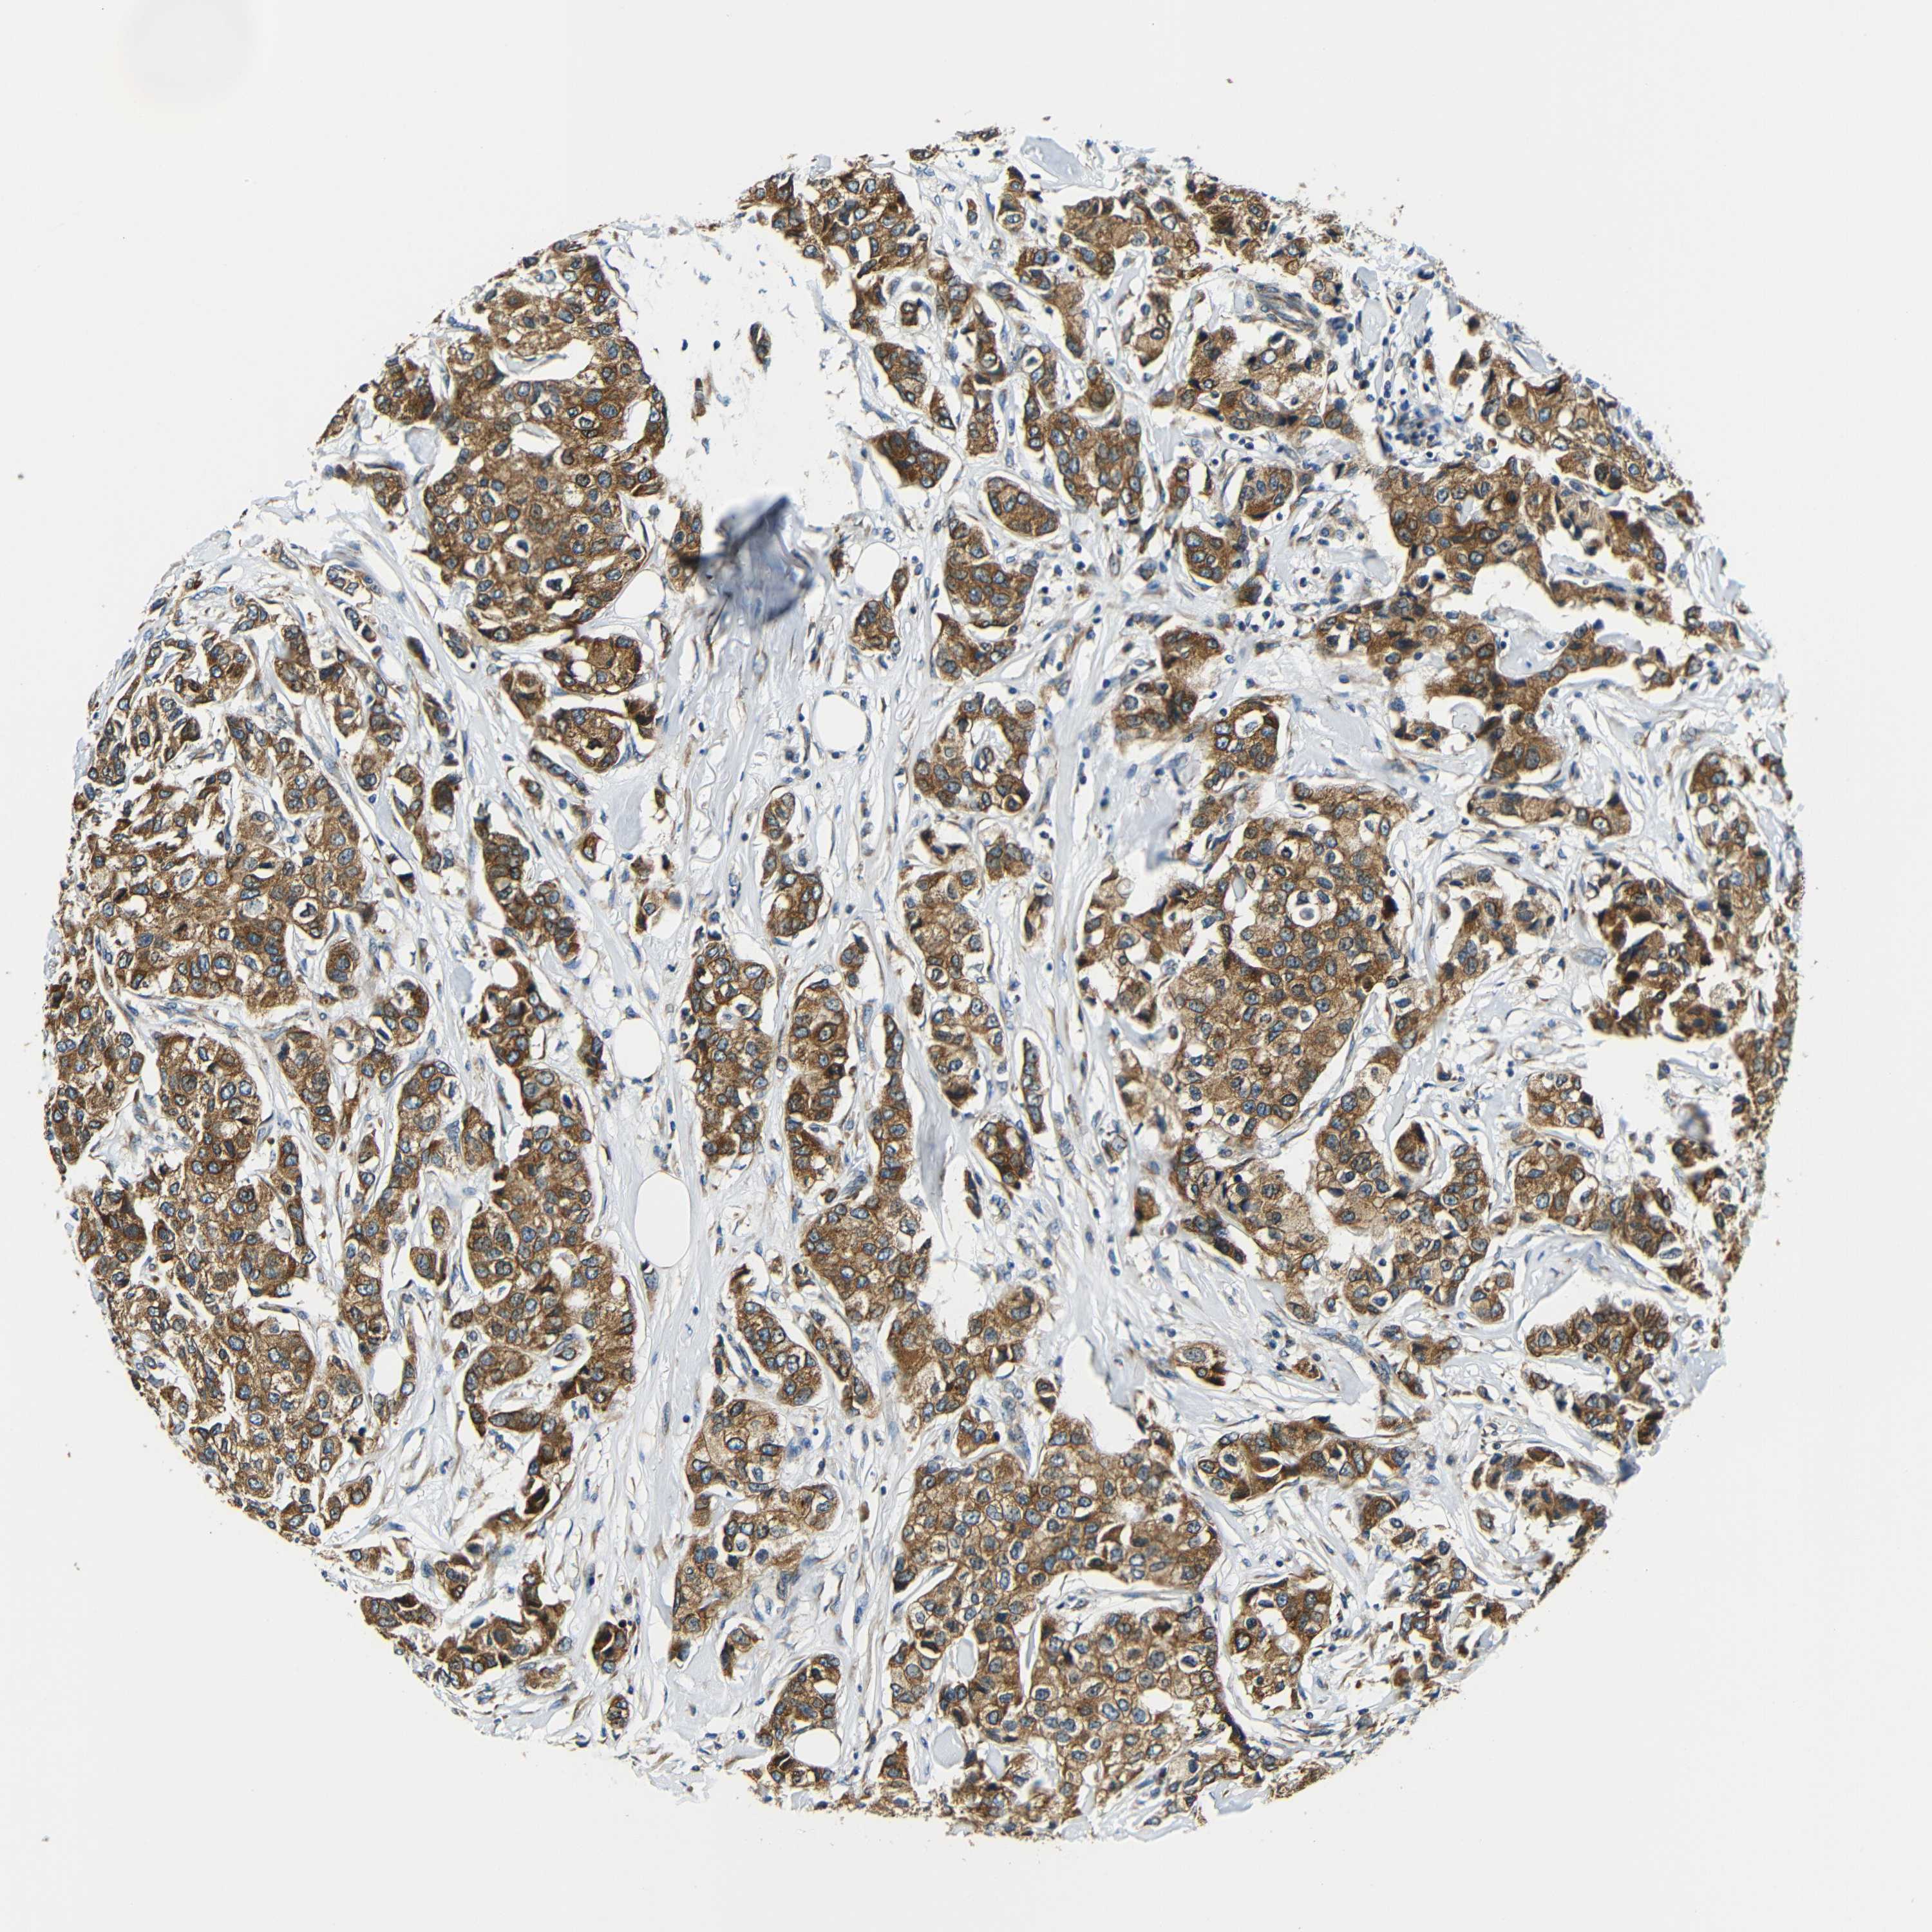

BRCA TCGA BRCA VALIDATION PROTEIN EXPRESSION